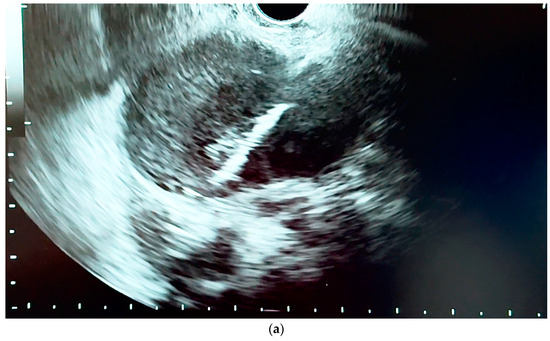

6.4.1. Endoscopic Ultrasound (EUS)